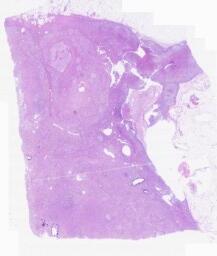

临床资料: 患者,男性,43岁,右侧肾上腺占位3+年入院,1+年以来逐渐发现高血压、高血糖、高血脂症,近期反复出现心悸、心慌伴头晕、乏力。CT示:右侧肾上腺外支结节状增粗,截面大小约30.5mm×18.8mm,密度不均,可见斑点状高密度影,增强扫描呈不均轻度强化。术中所见:右侧肾上腺外侧支可见大小约3×2cm类圆形肿物,与肝脏面腹膜粘连,质地较韧,术中触及肿瘤血压未见波动,切除肿瘤送检。

大体所见: 灰黄软组织一块,4.7×3.5×2cm,切开见一包块3.3×3×1.7cm,切面灰褐,实性,质中,边界清。